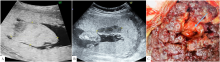

图2 病例3孕31<sup>+6</sup>周绒毛膜板下出血

注:A为胎盘前方近子面可见偏高回声,为绒毛膜板下出血,范围长径达11.5 cm,与正常胎盘组织有分界,有分层;B为中央型前置胎盘,绒毛膜板下出血位于胎盘脐带插入点附近;C为胎儿外生殖器呈"郁金香征";D为左侧子宫动脉可见切迹;E为出生后胎盘大体可见胎盘子面胎膜(羊膜+绒毛膜)与胎盘实质有分离,胎盘娩出过程中曾在其间积聚的不凝血已流失;F为出生后外生殖器证实为尿道下裂